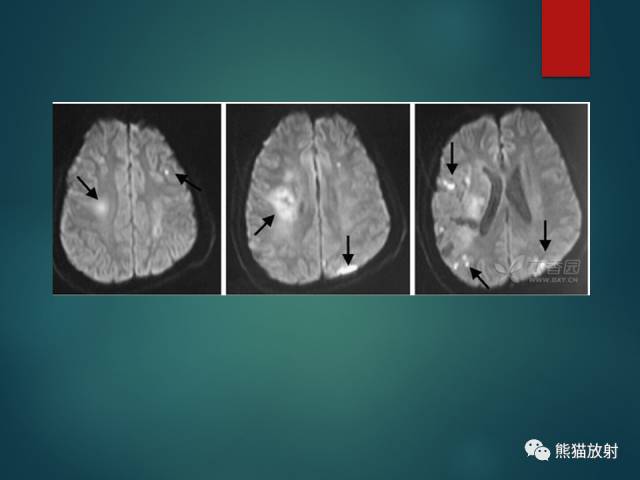

- 多发性硬化(MS):中青年女性;症状发作与缓解交替出现;直角脱髓鞘征;不同时期脱髓鞘斑块表现不一,急性期有强化。

- 脑白质疏松(LA):小动脉病变导致的白质纤维脱髓鞘;T2-FLAIR呈较高信号,DWI无弥散受限;常两侧对称,脑室周围明显。